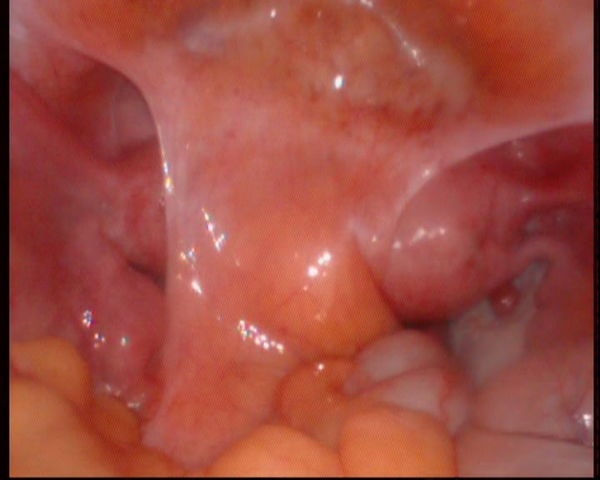

图2图3